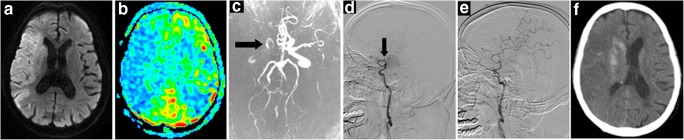

Fig. 3.

A 82-year-old woman (NO. 17 in Supplementary Tables 1 and 2) with a DWI-ASPECTS of 5 and an ASL-DWI mismatch ratio of 1.38 was treated by EVT alone and obtained successful reperfusion at 325 min from onset. This patient died of cerebral edema and herniation 10 days after intervention. a Infarction lesion presented on DWI (shown as high signal). b Hypoperfusion area shown on ASL-CBF map (blue). c Right ICA-MCA occlusion shown on MRA (black arrow). d DSA showing occlusion site of right ICA-MCA (black arrow) before EVT. e DSA showing reperfusion of occlusion vessel after EVT. f CT image at 24 h after EVT